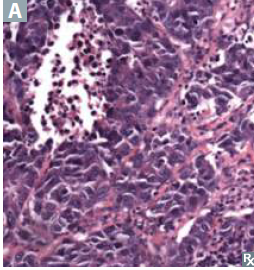

Centrally located Neoplasm of neuroendocrine KULCHITSKY cells ——> small dark blue cells. Chromogranin A +, neuron-specific enolase +

Small cell carcinoma